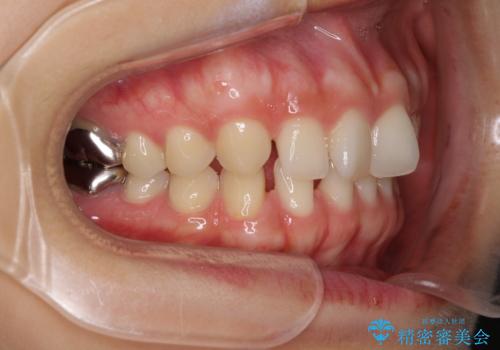

- 前歯の隙間と奥歯の目立つ銀歯を気にして来院された患者様です。

インビザラインにより下顎前歯の隙間を閉じるとともに、奥歯の咬み合わせを改善させることとしました。

矯正治療後には、銀歯のクラウンをセラミッククラウンへ替える補綴治療を行うこととしました。